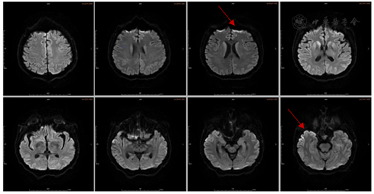

入院第6天查体较前变化体征为:双上肢肌张力略增高,双侧指鼻试验、轮替试验、跟膝胫试验等共济运动欠灵活,步态不稳,需搀扶,双侧腱反射对称(+++),双侧踝阵挛(+),双侧Babinski’s征(-),脑膜刺激征(-),余查体同前。入院第6d精神检查:神志淡漠,表情呆愣,多数时间下为亚木僵状态,对问话较前有反应,张口说话困难,反复提问下可回答几个字,对一些医生的交谈可以有笑容、自嘲的表现,对大多数交谈内容反应不明确;对命令要求可有反应,但难以配合;可疑认知功能减退(患者对检查欠配合),双手姿势怪异,无自知力。2020年12月15日头颅MRI示右侧额颞顶枕叶、左侧额叶、右侧尾状核头可见DWI高信号(图1)。于2020年12月15日转诊至外院神经内科就诊。

患者转院后表现查体:双肺呼吸粗,可闻及湿性啰音,余心腹系统等查体较前无明显变化。神经系统检查:无反应觉醒状态,不语,高级皮层功能检查不合作,颈强直,四肢肌张力高,双下肢腱反射(+++),右侧Babinski’s征(+),余查体不配合。患者头颅MRI、脑电图检查结果如图2,图3所示。脑脊液CSF结果显示:生化、常规、脑脊液病原学检查、自身免疫性抗体检查未见明显异常;脑脊液14-3-3蛋白阳性,朊蛋白(PRNP)基因突变阴性。

本例患者脑电图呈现有"周期性三相波",脑脊液中14-3-3蛋白阳性,头颅核磁影DWI显示有大脑皮质呈典型"花边征"及结合患者快速进展的临床症状考虑很可能为克雅氏病即Creutzfeldt-Jakob病(CJD)。

最后CJD典型辅助检查表现出现在不同的疾病时期,对临床甄别本病造成了一定困难。目前,CJD的确诊需要在死后或活检获得的脑组织中检测异常折叠的、CJD特异性蛋白酶耐药朊蛋白(PrPCJD),由于组织活检有感染病毒风险且活检程序繁琐、具有创伤性,因此,临床上对CJD的诊断往往具有挑战性。临床医生可以通过无创检查即脑MRI扫描、脑电图和脑脊液检查来协助诊断。头颅MRI:最早变化可出现在发病后1个月,并发生于脑电图及脑脊液出现异常结果之前;其敏感度及特异度可达到100%[1],少数患者早期可无异常改变。MRI的DWI相上可见对称或不对称性皮质"缎带征"或"花边征",基底节区(尾状核、壳核、丘脑枕)高信号对CJD早期诊断具重要意义[12]。FLAIR图像上双侧丘脑枕及丘脑背内侧的异常高信号为"丘脑枕征"和"曲棍球征"[1,5]。脑电图的早期敏感性一般但特异性较高,脑电图早期主要表现为非特异性弥漫性慢波及额部节律性6活动,中期则出现特征性的周期性尖慢复合波(为CJD标志性改变),至晚期则再次呈现非典型特征表现为类似昏迷状态的慢波及低电压活动[13]。本例患者在我院住院期间因配合度差未完成脑电图,故减少了诊断参考依据。最后对于脑脊液检查方面,随着病情进展,脑脊液蛋白数增加,目前唯一纳入WHO诊断标准中的分子蛋白是脑脊液中14-3-3蛋白。利用免疫方法检测脑脊液中14-3-3蛋白,在一定范围内该蛋白增加与患者典型临床表现增加呈正相关[14]。